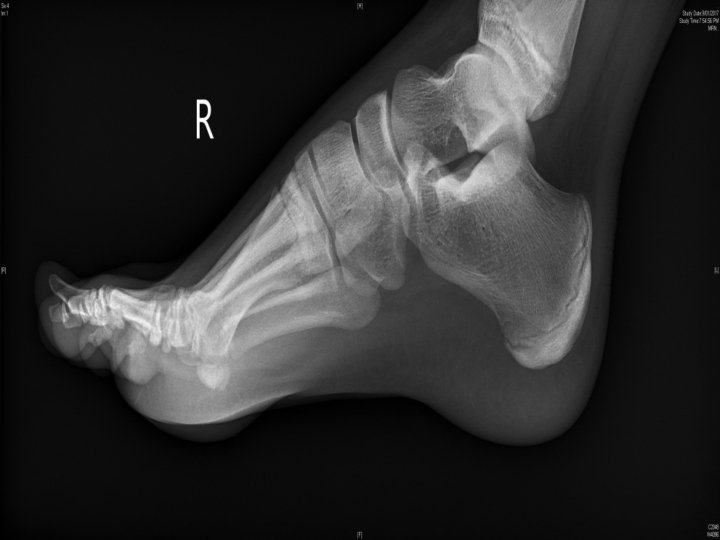

Sea urchin • • Most non venomous Sig pain if venom, rx with hot water immersion XR/USS for retained spines Can be observed for ongoing pain +/- surgical removal